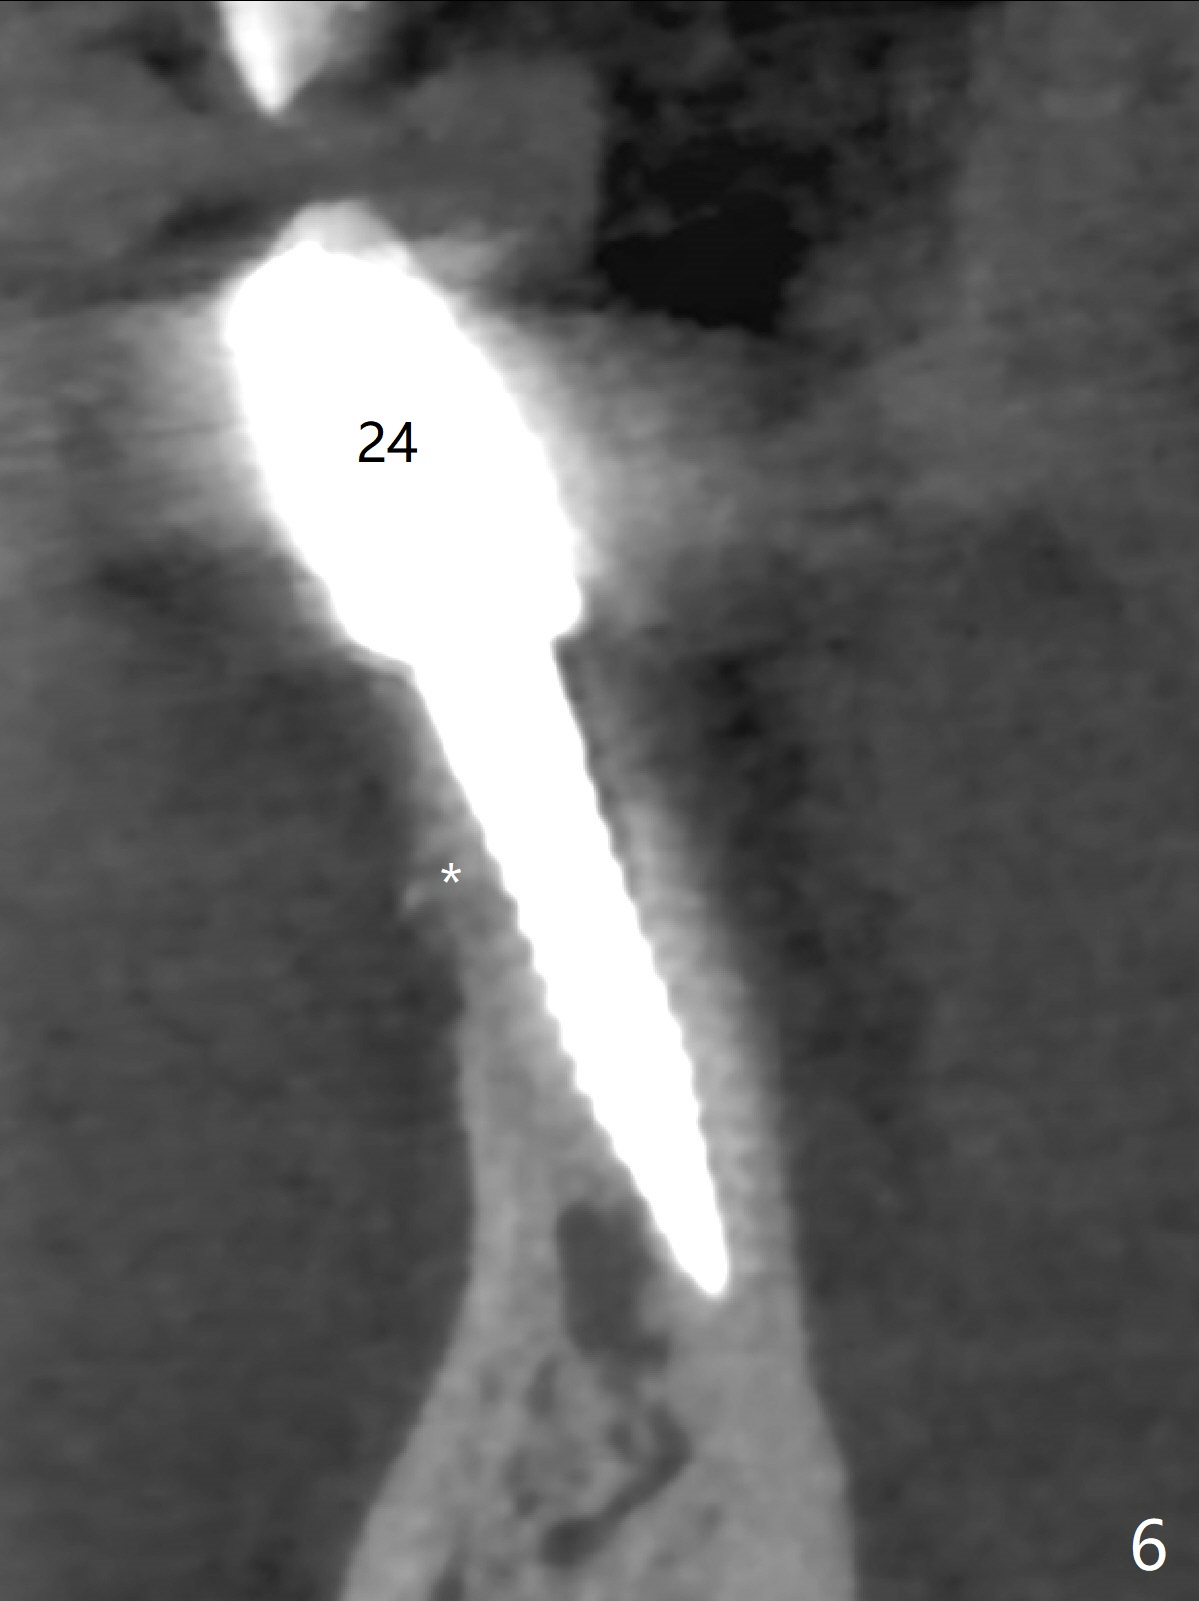

The fenetration found buccal to #25 two months post cementation persists, although asymptomatic, 4 months post cementation. Blood is drawn for PRF. In fact the implants at #24 and 25 are exposed buccal; there is limited amount of the buccal bone (Fig.1 *). After granulation tissue removal, Titanium brush is used to clean the implant threads. Allograft and Osteogen are mixed with PRF liquid to form gel, which is placed over the exposed implant threads. The bone graft is covered with a piece of PRF membrane and a piece of collagen membrane (Fig.2 C). Immediately postop PA (Fig.3) and CBCT (Fig.4) show that the implants have sufficient clearance between them. The implant thread exposure is most likely due to failure to place the implants deep enough and the implants are slightly large relative to the ridge (Fig.5-8). If the bone graft does not heal, new type of 1-piece implants (Fig.9,10 (green) smaller in diameter, 2 or 2.5 mm ) with longer abutment (pink) will be placed subcrestal buccal with guide.